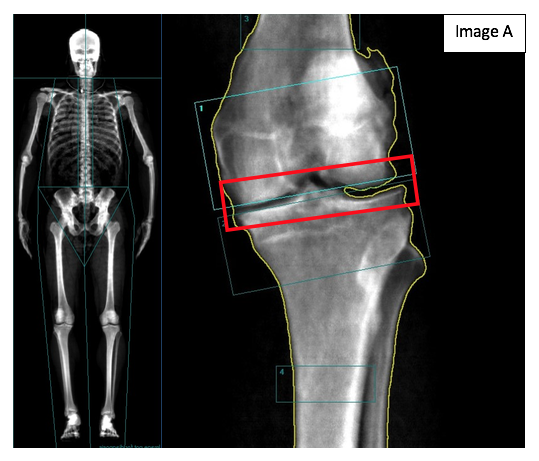

In the image below (Image A), you see the pre-surgical DXA total skeletal scan as well as the isolated left knee DXA scan. In the pre-surgical isolated knee view, you can see the accumulated damage that has occurred in the joint area over the years (highlighted by the red box). It should be noted that a DXA scan would not be used to diagnose whether a replacement is necessary or not. In most cases, an X-ray and/or magnetic resonance image (MRI) would be used by an orthopedic surgeon to diagnose the need for a knee replacement as well as the type of knee replacement required.

Two things stick out for me regarding the DXA scans below. The first is that, even though it is not used to diagnose whether a knee replacement is appropriate, the DXA scan was, in fact, able to pick up the damage that made a knee replacement necessary. The second is the potential to use the DXA to monitor the health of the bone surrounding the knee replacement. Over time, subsequent scans of this individual and others like him will be useful in determining the benefits of DXA technology in monitoring long-term recovery as it relates to bone health.